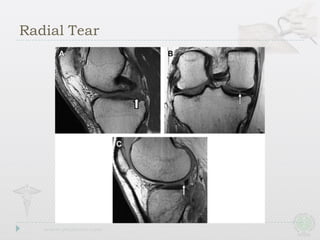

Radial Tear

Radial Tears

• Also involvefree edge,but path is perpendicular to long axis • Drastically affect ability to resist hoop stresses • Deeper the tear,the more drastic the biomechanical consequences Radial Tears